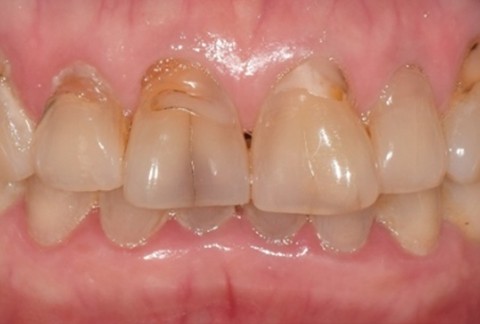

임플란트-전후사진